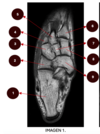

Nombre de estructuras

Rojo: Escotadura sigmoidea radial Azul: Cabeza cubital Amarillo: Silla cubital Rosa: Fóvea Verde: estiloides